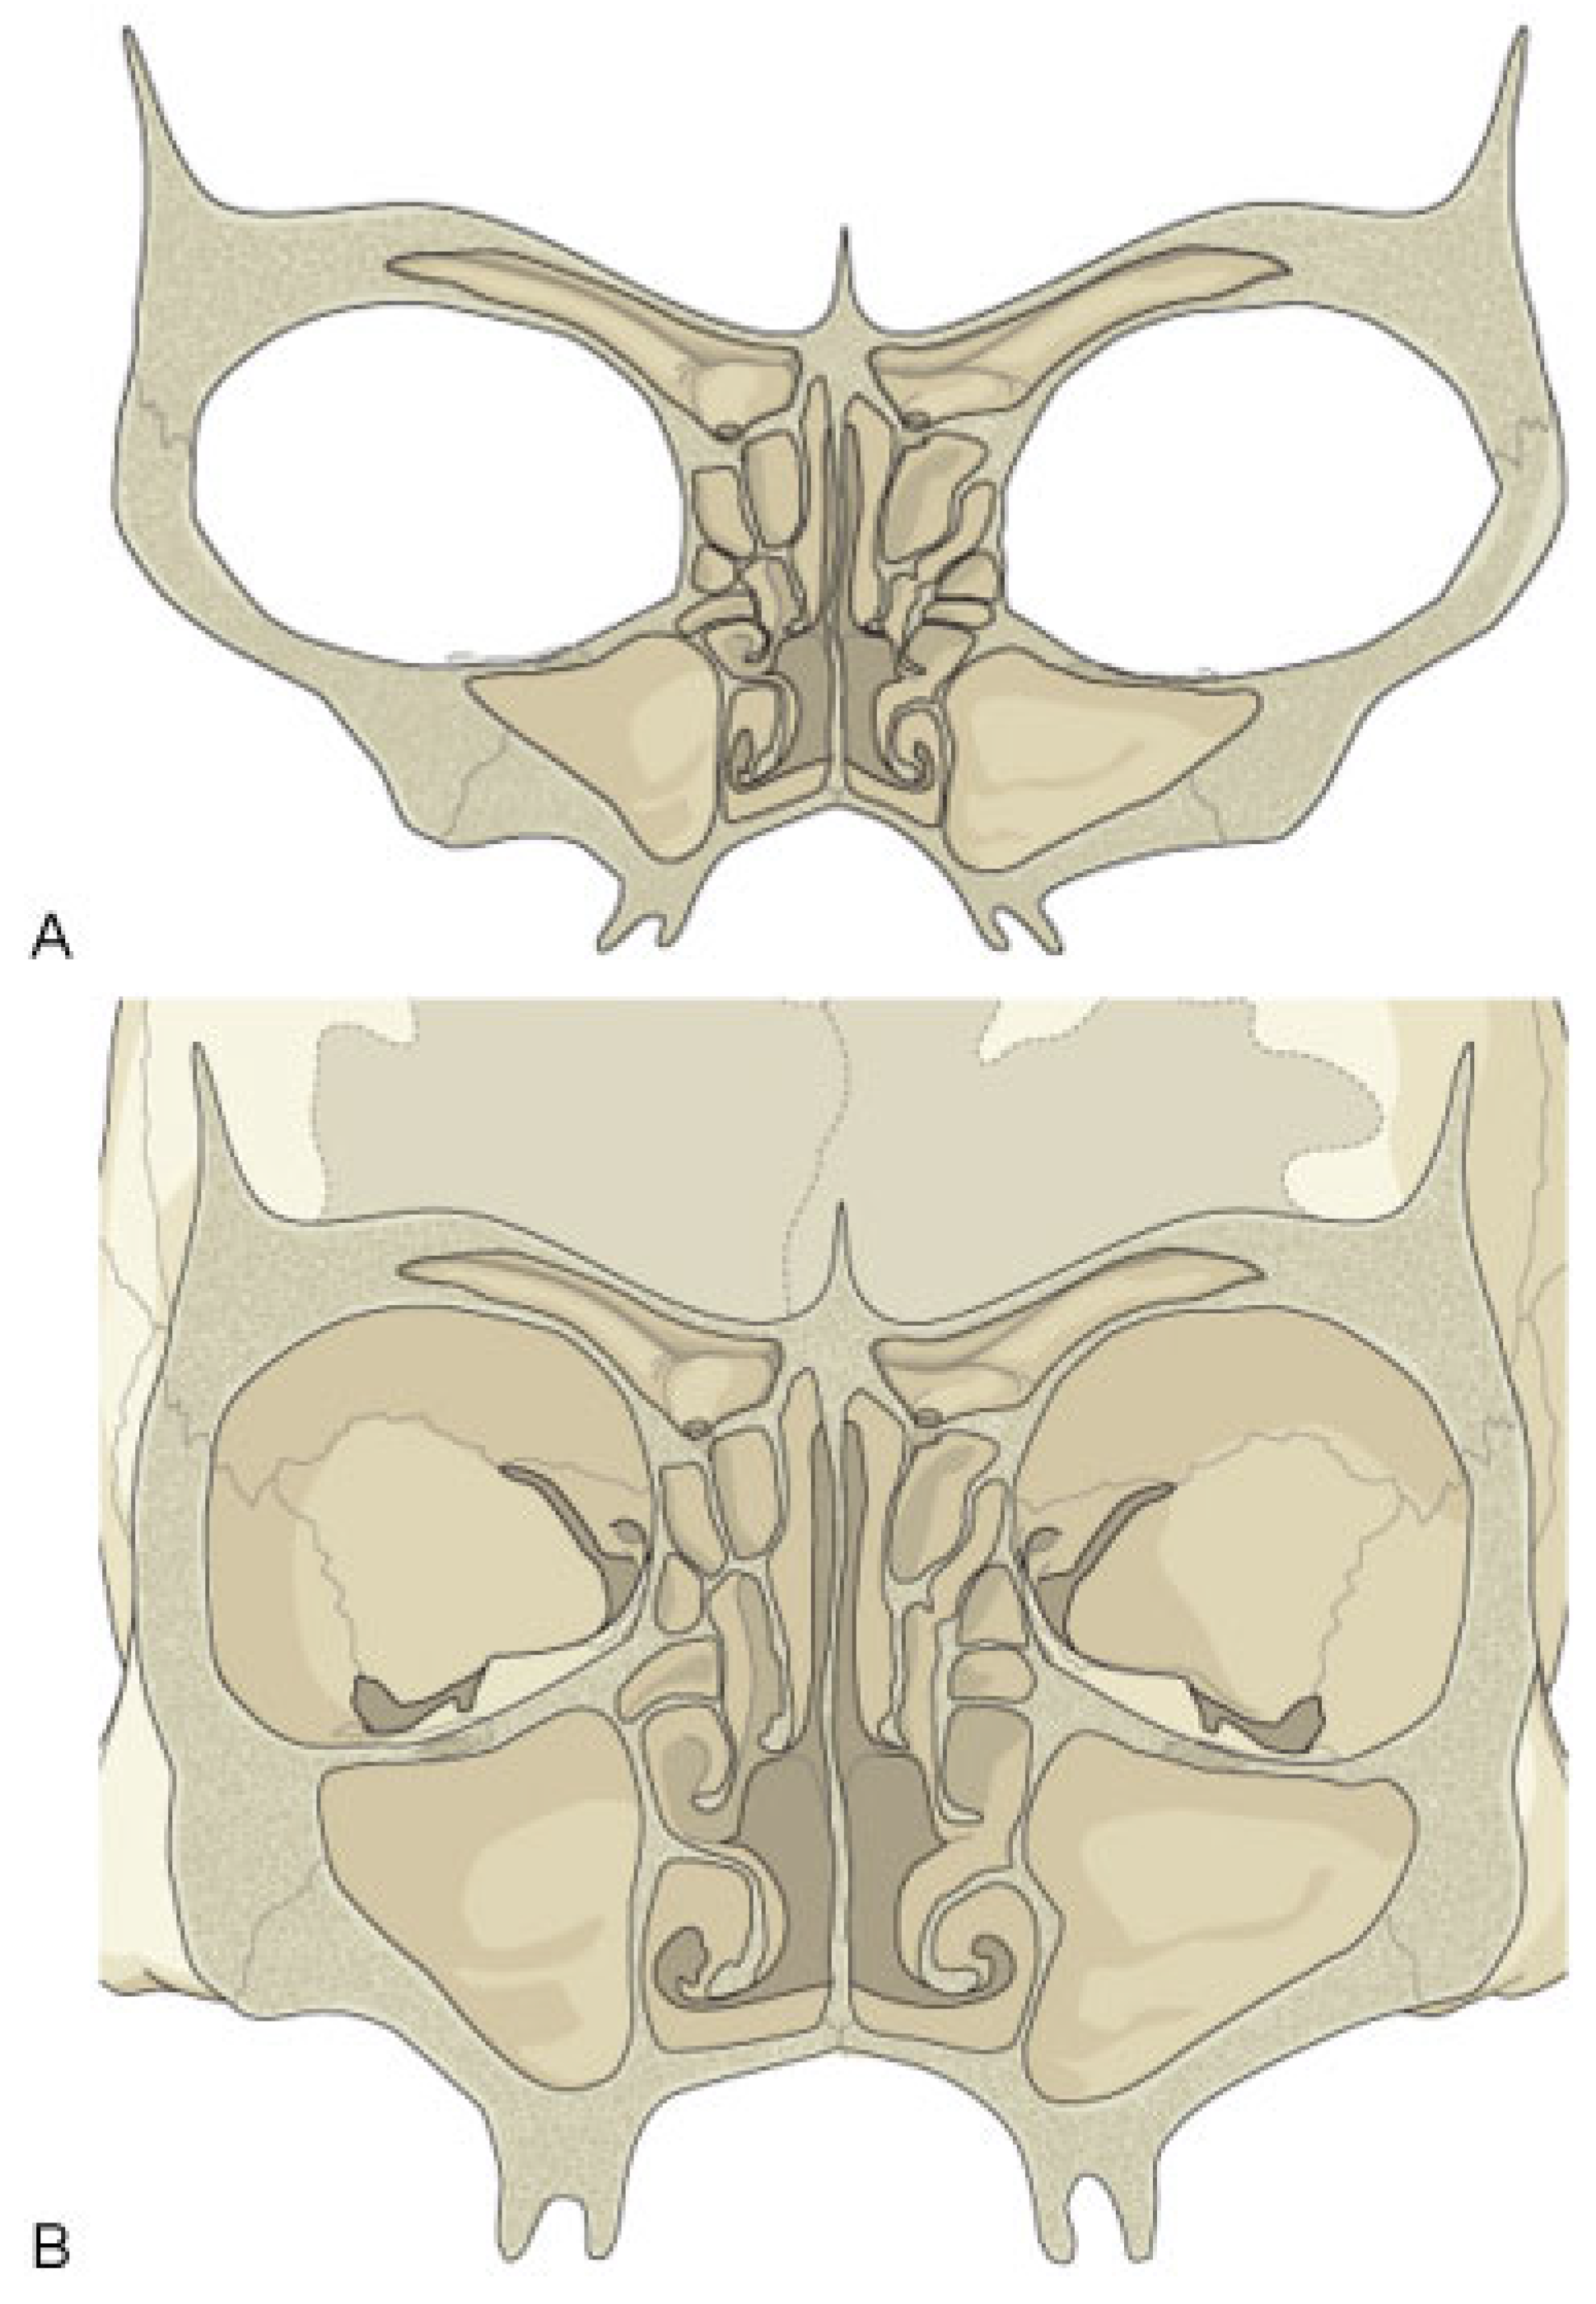

Seven bones make up the orbit: frontal, maxilla, zygoma, ethmoid, lacrimal, greater and lesser wings of the sphenoid, and palatine. The outer rim of the orbit is comprised of the first three robust bony elements, protecting the more delicate internal bones of the orbital cavity. The orbital cavity is itself bound by the orbital roof, lateral and medial walls, and orbital floor. Some of these boundaries display changes in structural integrity—closely related to sinus pneumatization—during different stages of development. On viewing the cross-sectional anatomy of pediatric and adult skulls (Figure 1), the striking bony differences that occur with sinus development become obvious, revealing their relative strengths and weaknesses.

Figure 1. Coronal sections of the pediatric and adult orbit. (A) The thick pediatric orbital floor is contrasted with its diminutive orbital roof. (B) The delicate nature of the adult orbital floor and medial wall is apparent.